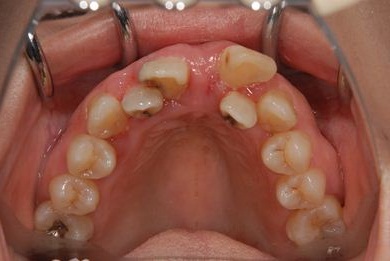

抜歯即日スピードインプラント治療

| 性別/年齢 | 女性 / 52歳 | ||||||||||||||||||||||||||||||||

| 主訴 | 歯周病で歯の位置がずれてしまった。 | ||||||||||||||||||||||||||||||||

| 治療内容 | インプラント2本(抜歯即日スピードインプラント)、メタルボンドセラミッククラウン4本 | ||||||||||||||||||||||||||||||||

| 総治療費 | 1,269,450円 | ||||||||||||||||||||||||||||||||

| 治療期間 | 10ヶ月 |